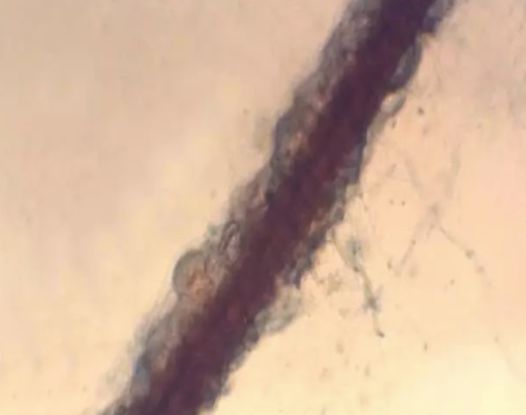

79. 腋毛菌感染(光镜-毛发表面菌丝)